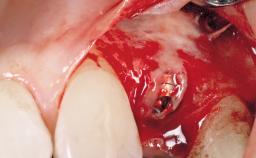

Placement Protocol Immediate implant placement

Socket Morphology Single-root socket

Socket Integrity Sufficient, with intact bone walls

Bone Volume Sufficient, with intact walls